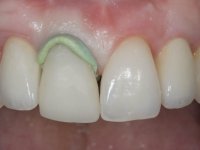

Após 5 anos da primeira intervenção, a paciente surge na consulta com uma peri-implantite nos implantes colocados no local dos dentes 1.2 e 4.6. Começamos por abordar a peri-implantite no local do dente 2.2. Foi feita uma ponte provisória de laboratório em acrílico com 2 elementos. O dente 1.1 como pilar e o 1.2 como pôntico, este último apresentava um apoio distal. A coroa do 1.2 foi removida do coto com um corte longitudinal feito com turbina e depois foi fraturada com um mini luxador. O coto foi de seguida desaparafusado do implante. Fez-se o mesmo procedimento para remover a coroa do 1.1. O dente 1.1 foi re-preparado e a ponte provisória foi rebaseada em boca com acrílico autopolimerizável. Feito o correto acabamento e polimento da provisória foi feita a sua cimentação temporária com cimento de policarboxylato. Numa consulta posterior. foi feita a remoção da ponte provisória, feita a cirurgia para explantação do implante, colocou-se um novo implante e fez-se a regeneração óssea da zona com uma membrana não reabsorvível. 3 meses após foi removida a coroa do implante colocado no 4.6. Foi feito um corte horizontal com turbina na zona cervical e com um mini luxador descolou-se a coroa do coto. Após este procedimento fez-se a explantação do implante. Após 6 meses foi colocado um novo implante no local do 4.6. Após a osteointegração foi feita a impressão com a técnica de moldeira aberta e foi confecionada em laboratório uma coroa aparafusada sobre o implante. Aprovada pela paciente foi apertada definitivamente em boca. Após 1 mês removemos a ponte provisória antero-superior, reforçamos o dente 1.1 com um poste intra- radicular e reconstruimos o coto com uma resina de polimerização dual. Nessa mesma consulta expomos o implante colocado no 1.2 e fizemos uma impressão pela técnica de moldeira aberta com silicone de dupla viscosidade e presa rápida. No laboratório foi feita uma ponte provisória de 2 elementos, aparafusada sobre o implante e cimentada sobre o dente. A primeira ponte provisória foi removida e colocada a segunda aparafusada sobre o implante. A linha de acabamento cervical do 1.1 foi rebaseada com resina composta durante o aperto do parafuso do implante. Depois foi removida, foram feitos os acabamentos e finalmente apertada sobre o implante e cimentada temporariamente sobre o dente. Após 2 meses de maturação dos tecidos moles em função do perfil de emergência criado pela nova ponte provisória, pudemos avaliar a estética conseguida em conjunto com a paciente. Neste longo processo o dente 2.1 teve que fazer um tratamento endodôntico. Decidiu-se assim fazer também uma coroa no dente 2.1.O dente 2.1 foi preparado na mesma consulta em que se fez a impressão ao implante. A ponte provisória foi utilizada para individualizar a peça de transferência, copiando o seu perfil de emergência e em seguida foi realizado o afastamento gengival com caolino. A impressão foi feita com a técnica de moldeira aberta com silicone de dupla viscosidade e presa rápida. Após a escolha da cor, a impressão foi enviada  para o laboratório onde foram confecionadas 2 coroas  com infraestrutura em Zr. revestidas a cerâmica para os dentes 1.1 e 2.1 e uma coroa aparafusada sobre o implante no dente 1.2. O trabalho final foi aprovado pela paciente e foi colocado definitivamente em boca. A coroa sobre o implante foi aparafusada com 35 N e as coroas foram cimentadas com cimento de ionómero de vidro reforçado com resina.